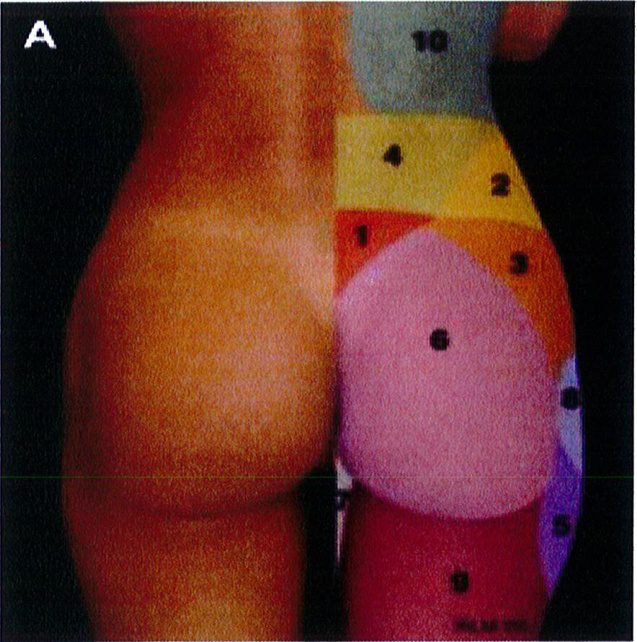

Các đơn vị thẩm mỹ vùng mông là khái niệm quy định các vùng thẩm mỹ khác nhau của mông. Hiểu được các đơn vị thẩm mỹ này và mối quan hệ của chúng với khu- ng chậu là điều tối quan trọng trước khi thực hiện nâng mông. Các đơn vị này được sử dụng để định hướng và xác định khu vực nào sẽ được nhận Mỡ, khu vực nào sẽ được hút mỡ, điều này sẽ ảnh hưởng tới kết quả, vì thế chúng ta cần thảo luận kỹ. Công trình đã xuất bản trước đây đã mô tả 10 đơn vị thẩm mỹ cho vùng sau (Hình 2), và một công trình khác đã mô tả 8 đơn vị thẩm mỹ vùng mông: 2 đơn vị mạn sườn, 1 đơn vị tam giác cùng, 1 đơn vị

Hình. 3. 8 đơn vị thấm mỹ vùng mông bao gôm 2 mạn sườn đối xứng 2 bên (1,2), 1 tam giác cùng (3), mông hai bên (4,5), 2 đùi sau đối xứng nhau (7 và 8), và 1 bộ phận giao thoa của 2 nếp lắn mông (hình thoi – 6) (Nguồn: Centeno RF. Gluteal aesthetic unit classification: a tool to improve outcomes in body contouring. Aes- thetic Surg J 2006;26(2):200-8)